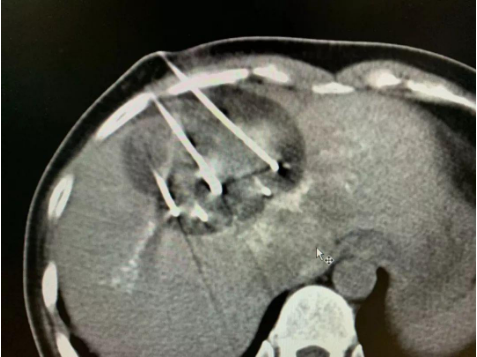

因为肝上的肿瘤比较大,血运很丰富,所以,复大的专家团队首先为她做了介入栓塞治疗。然后第二步,为她做了冷冻消融。接着,在椎体上的肿瘤做了冷冻加粒子植入。

做完治疗两周以后,再复查CT,肿瘤基本上都坏死了。作为一名影像学专家,苏女士自己看了片子以后,对自己的治疗效果非常满意。